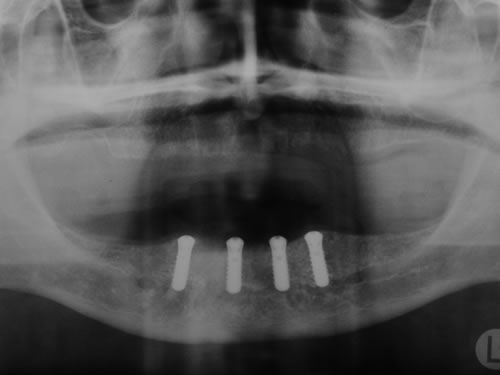

Bei der ersten Untersuchung in der Praxis hat Frau W. zunächst den Anamnesebogen ausgefüllt. Sie ist nie ernstlich krank gewesen und nimmt nur gelegentlich eine Kopfschmerztablette. In einem ausführlichen Gespräch berichtet sie ihrem Zahnarzt über die Schwierigkeiten mit den Prothesen. Nach einer ersten Untersuchung kann ihr der Zahnarzt Mut machen. Die Kieferverhältnisse sind zwar sehr ungünstig, doch so, dass eine Einpflanzung noch möglich ist. Die vorhandenen Prothesen weisen keine Mängel auf, finden aber keinen Halt. Beide Prothesen sollen nach der Einpflanzung weiter getragen werden. Nach einem Kieferabdruck wird eine Platte für den Unterkiefer angefertigt, auf der Metallkugeln befestigt sind. Sie wird wie eine Prothese eingesetzt, und es wird eine Röntgenaufnahme gemacht, die anschließend vom Zahnarzt genau vermessen wird. Es ergibt sich, dass noch eine Resthöhe von 15 mm vorhanden ist. Da auch die Breite des Kiefers ausreicht, wird ihr die Einpflanzung von vier künstlichen Zahnwurzeln empfohlen. Für ihre spezielle Kieferform ist dies die beste Lösung.

Für den Oberkiefer ist eine CT-Untersuchung notwendig, die ebenfalls mit einer Schablone durchgeführt wird. Auswertung, Planung und Implantations-Simulationen ergeben, dass sechs Implantate im vorderen Kieferabschnitt verankert werden können. Auch die Qualität des Knochens lässt eine Einpflanzung ohne weitere Maßnahmen zu. Diese Behandlung soll nach der Versorgung des Unterkiefers erfolgen.